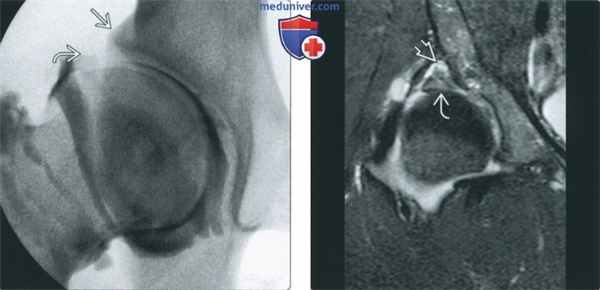

(Слева) Артрография, передне-задняя проекция, пациент 18 лет: визуализируется неглубокая вертлужная впадина со скошенным кверху латеральным краем. Дефект наполнения соответствует увеличенной суставной губе («лимб»).

(Справа) МР-артрография в режиме Т2ВИ FSE FS, коронарный срез, пациент 25 лет: наблюдается неглубокая вертлужная впадина. Видны разрыв суставной губы, пара-лаоральная киста и обширные дегенеративные изменения лимба суставной губы.